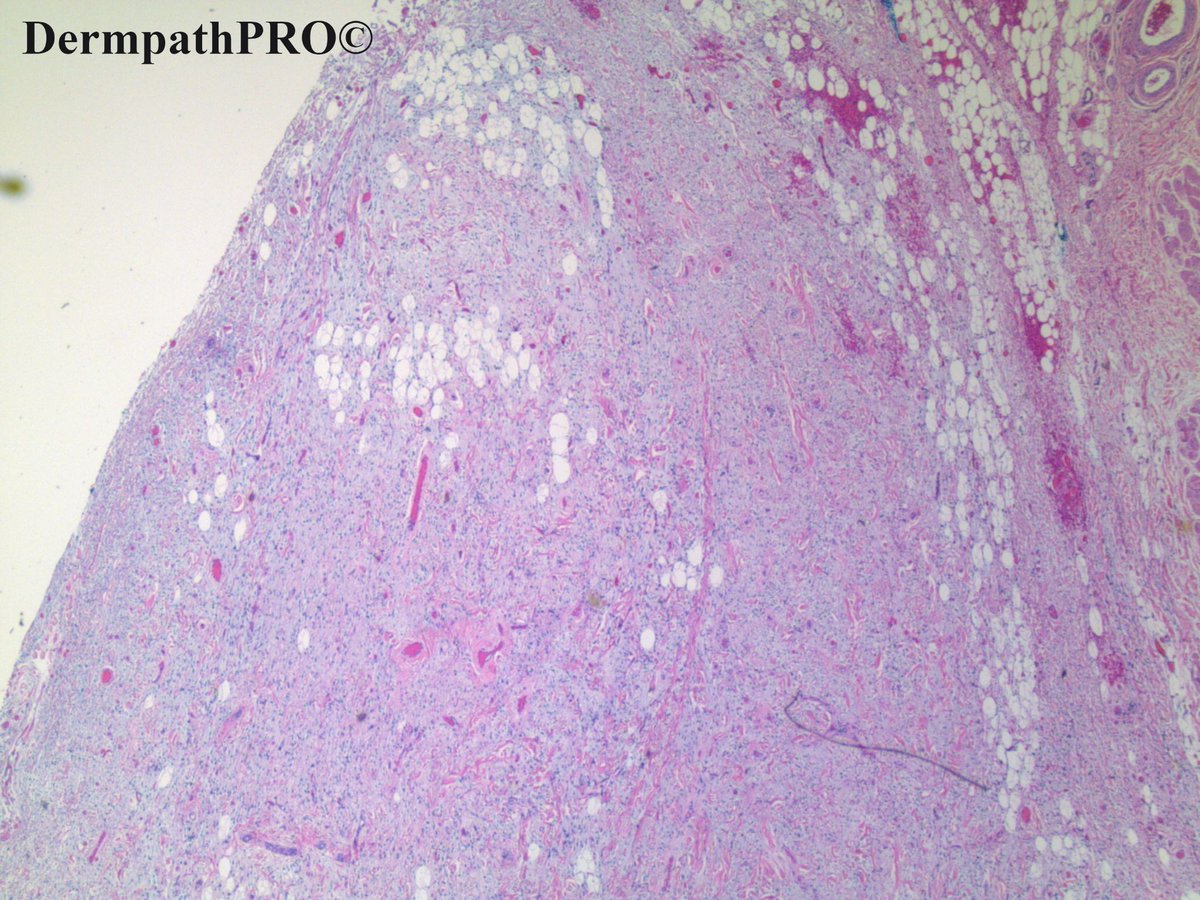

Case: 2729 - 22 December 2020

History: 69 year old male with caruncular lesion.

Posted By: Dr. Uma Sundram